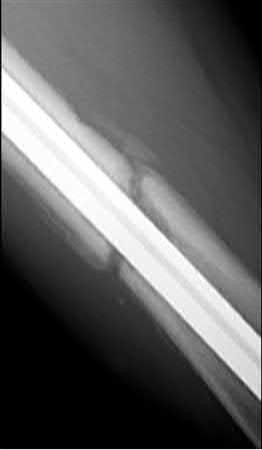

What is the most common type of malalignment after intramedullary nailing of distal 1/3 extra-articular tibia fractures using a infrapatellar approach when compared with plating?

The most common type of malalignment after intramedullary nailing of distal 1/3 extra-articular tibia fractures using an infrapatellar approach when compared with plating is valgus malalignment.

Fixation of distal one-third tibial shaft fractures can be successfully treated with either intramedullary nailing or plating. The literature describes advantages and disadvantages to both approaches, however intramedullary nailing has been shown to lead to increased rates of valgus malunion. Recent studies have shown that using a suprapatellar approach may decrease the incidence of valgus malalignement.

Primary angular malalignment was identified in 17 patients (16.3%). This included four patients treated with tibial plating (8.3%) and 13 patients treated with nails (23%, P = 0.02). Eight of these (7.7% of all patients) had malalignment between 6° and 10° of angulation. Valgus was the most common

angular deformity, accounting for 70% of angular deformity cases.